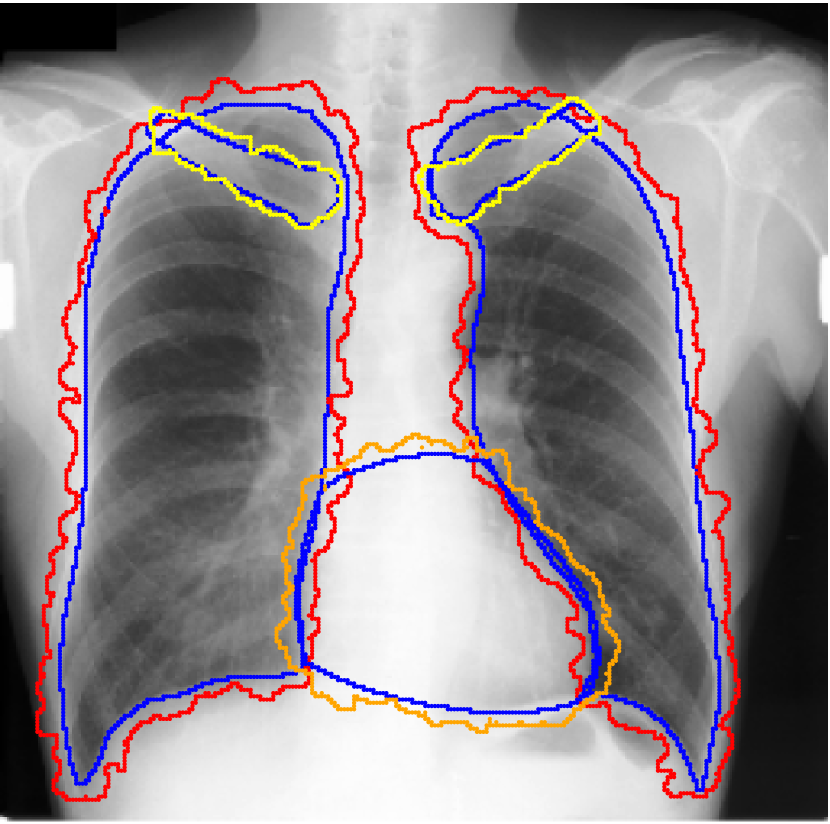

Real-world label noise. To evaluate with real-world label noise is challenging. We are not aware of any public medical image segmentation dataset that has both true labels and noisy labels from human annotators. Therefore, we use a multi-annotator dataset, LIDC-IDRI dataset (Armato III et al., 2015; Armato et al., 2011; Clark et al., 2013), and the coarse segmentation in a vision dataset, Cityscapes (Cordts et al., 2016). The LIDC-IDRI dataset consists of 1018 3D thorax CT scans where four radiologists have annotated multiple lung nodules in each scan. The dataset was annotated by 12 radiologists, and it is not possible to match an annotation to an expert. We use the majority voting as the true labels and the union of four annotations as noisy labels. We process and split the data exactly the same way as Kohl et al. (2018). Cityscapes dataset contains 5000 finely annotated images along with a coarse segmentation by human annotators that we use as the “noisy label”. We only focus on the ‘car’ class because (1) cars are popular objects and are frequently included in images; (2) the coarse annotation of cars is very similar to noisy annotation in medical imaging – they are reasonable distortions of the clean label without changing the topology. See Figure 4(c) for an example. The detailed settings of LIDC-IDRI and Cityscapes can be found in Appendix A.2.1.

Table 1 shows the segmentation results of different methods with synthetic noisy label settings on JSRT , ISIC 2017 and Brats 2020 dataset. Note that QAM cannot be applied to Brats 2020 dataset because their network is designed for 2D only. We compare DICE score (DSC) on testing sets (against the clean labels). For each setting, we train 5 different models, and report the mean DSC and standard deviation. In and , where biases show up in noisy labels, the proposed method outperforms the baselines by a big leap in total case. The compared methods, however, only work when little bias is included, like . is equivalent to setting in our Markov model, resulting in . We also test the proposed method on real-world label noise, results shows in Table 2. Figure 5 shows examples of label correction results. We provide more qualitative results in the Appendix A.4.

A.4 Qualitative Results

We provide qualitative results for prediction on test images in Fig. A.6 and Fig. A.7 as two sub parts. We also show the label correction on training images in Fig. A.5.